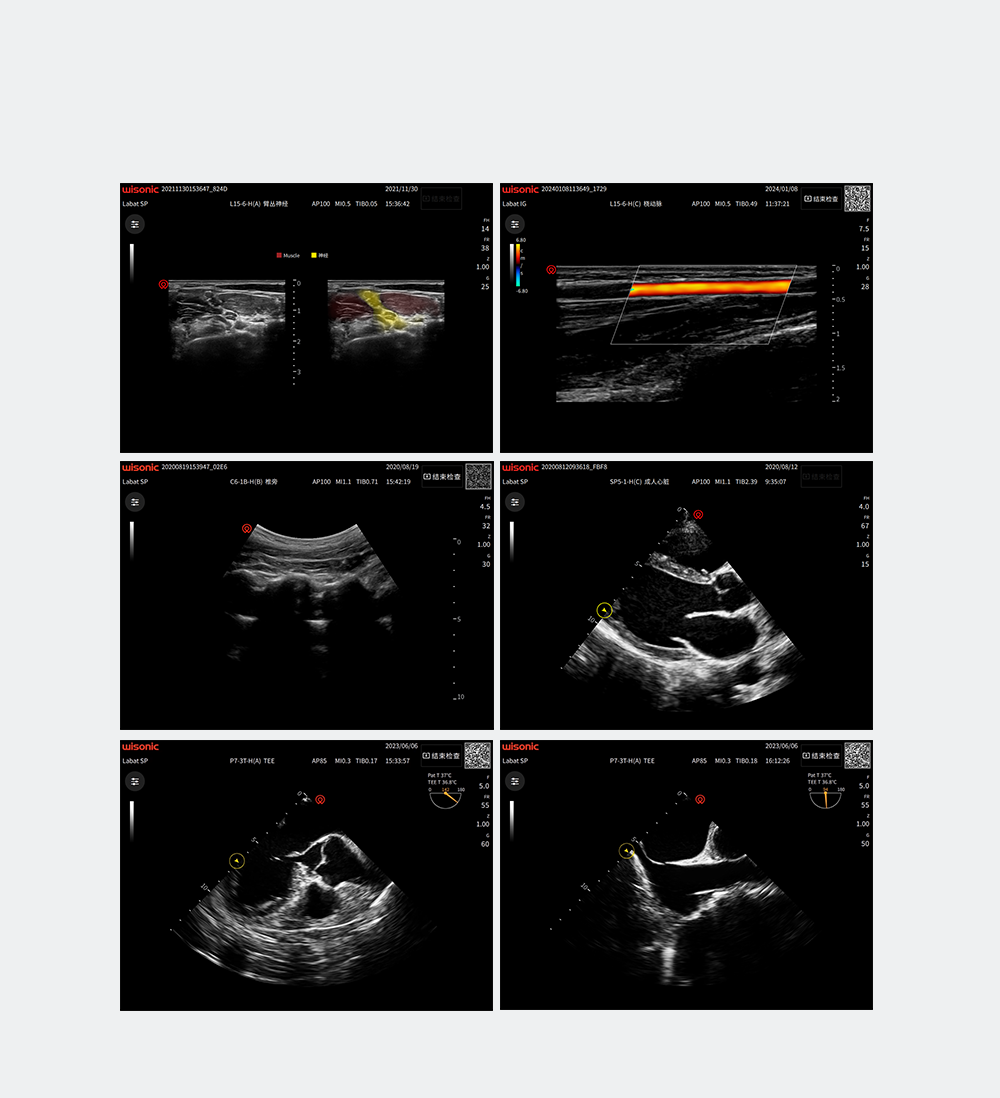

wiNerve

AI Intelligent Nerve Recognition

Real-time Recognition

Cloud Solution

Support Multiple Nerves

Labat Probe Family

Full-range probes for versatile applications

Excellent Clinical Images

Application pictures